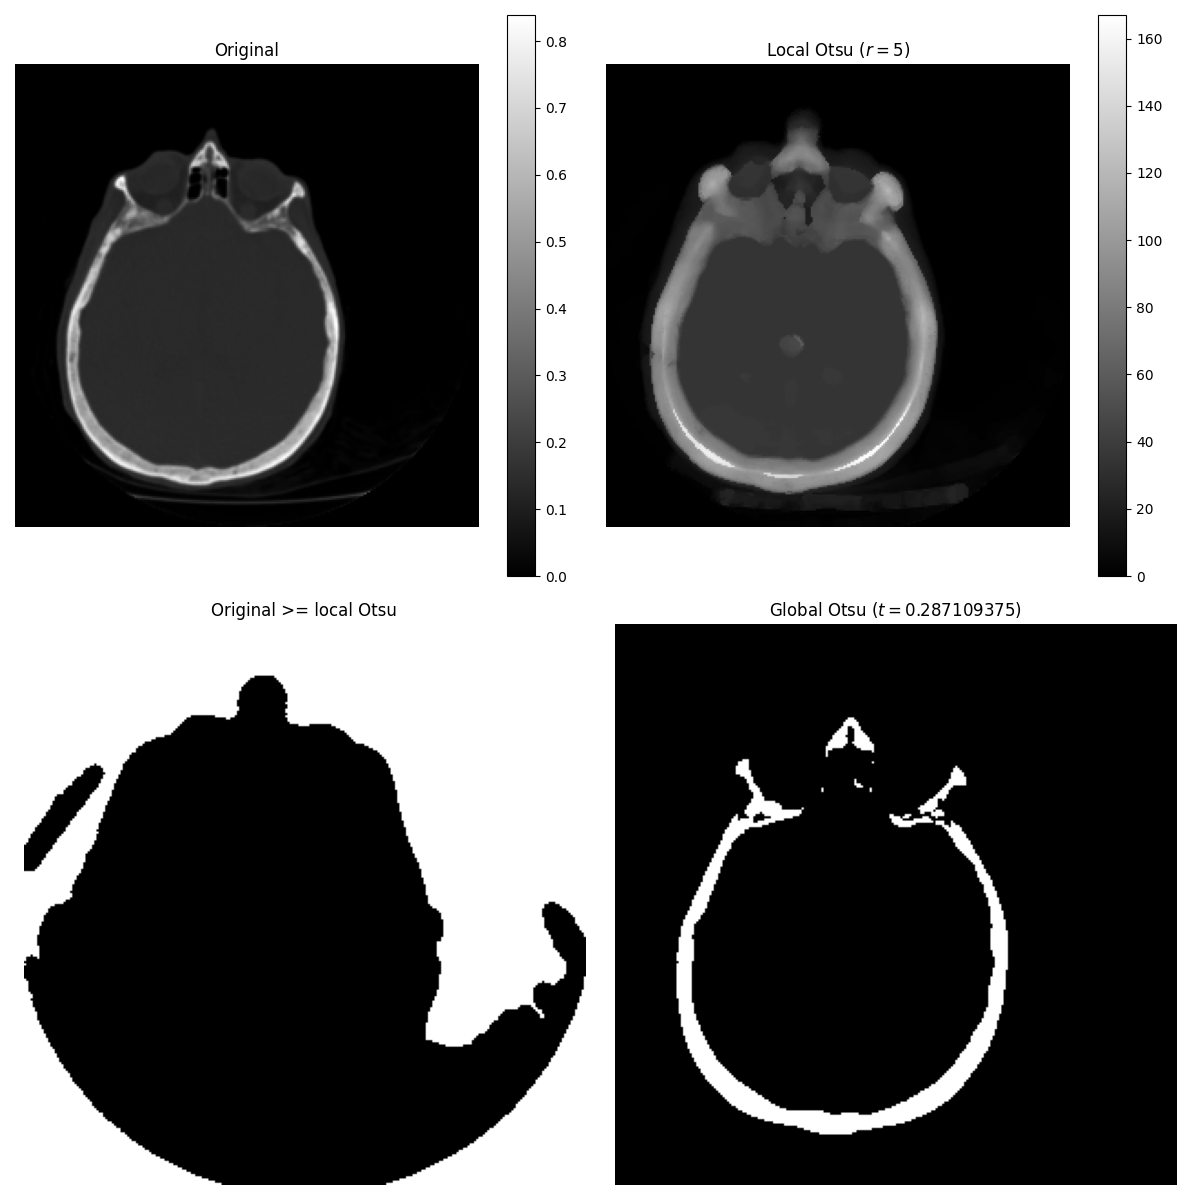

The Otsu threshold method [5] can be applied locally using the local gray-level distribution. In the example below, for each pixel, an “optimal” threshold is determined by maximizing the variance between two classes of pixels of the local neighborhood defined by a structuring element.

These algorithms can be used on both 2D and 3D images.

The example compares local thresholding with global thresholding, which is

provided by skimage.filters.threshold_otsu(). Note that the former is

much slower than the latter.

The example below performs the same comparison, using a 3D image this time.

brain = ski.exposure.rescale_intensity(ski.data.brain().astype(float))

radius = 5

neighborhood = ski.morphology.ball(radius)

# t_loc_otsu is an image

t_loc_otsu = ski.filters.rank.otsu(brain, neighborhood)

loc_otsu = brain >= t_loc_otsu

# t_glob_otsu is a scalar

t_glob_otsu = ski.filters.threshold_otsu(brain)

glob_otsu = brain >= t_glob_otsu

fig, axes = plt.subplots(nrows=2, ncols=2, figsize=(12, 12), sharex=True, sharey=True)

ax = axes.ravel()

slice_index = 3

fig.colorbar(ax[0].imshow(brain[slice_index], cmap=plt.cm.gray), ax=ax[0])

ax[0].set_title('Original')

fig.colorbar(ax[1].imshow(t_loc_otsu[slice_index], cmap=plt.cm.gray), ax=ax[1])

ax[1].set_title(f'Local Otsu ($r={radius}$)')

ax[2].imshow(brain[slice_index] >= t_loc_otsu[slice_index], cmap=plt.cm.gray)

ax[2].set_title('Original >= local Otsu')

ax[3].imshow(glob_otsu[slice_index], cmap=plt.cm.gray)

ax[3].set_title(f'Global Otsu ($t={t_glob_otsu}$)')